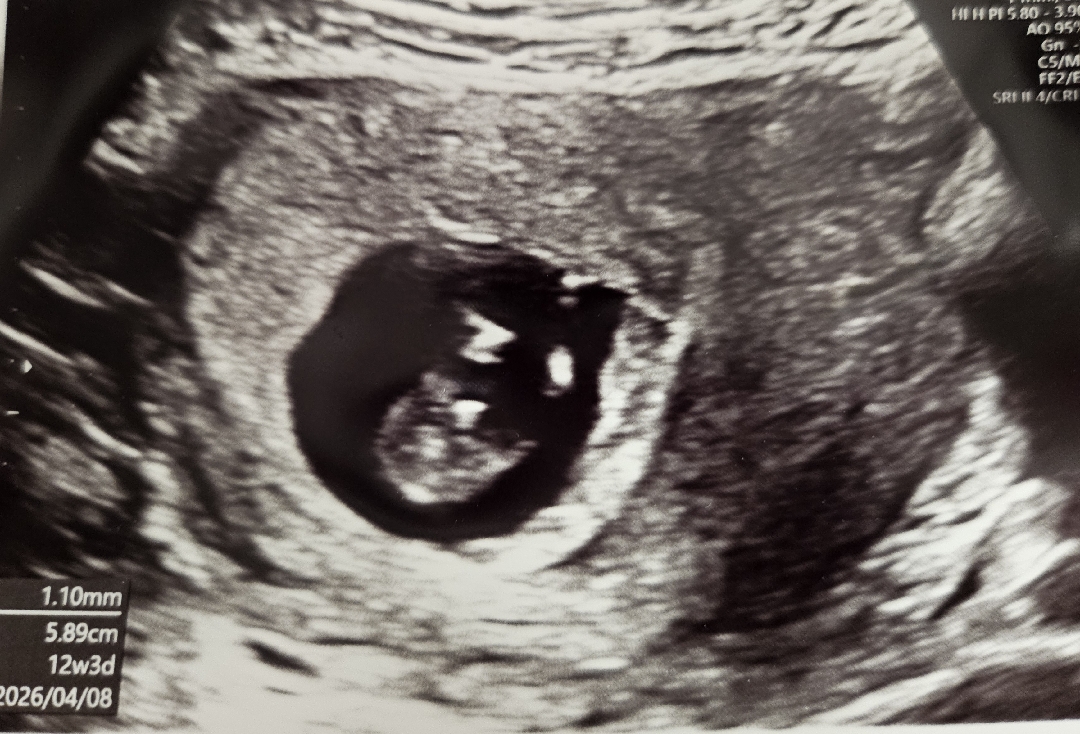

애기는 12주 넘어선 크기에요ㅎ의사선생님은 다리 사이 보시곤 탯줄은 아닌것 같다하셨어요 아들일 가능성이 크다하셨는데 성별 반전없이 아들일까용😅 사진은 다리 사이 사진입니당ㅎ